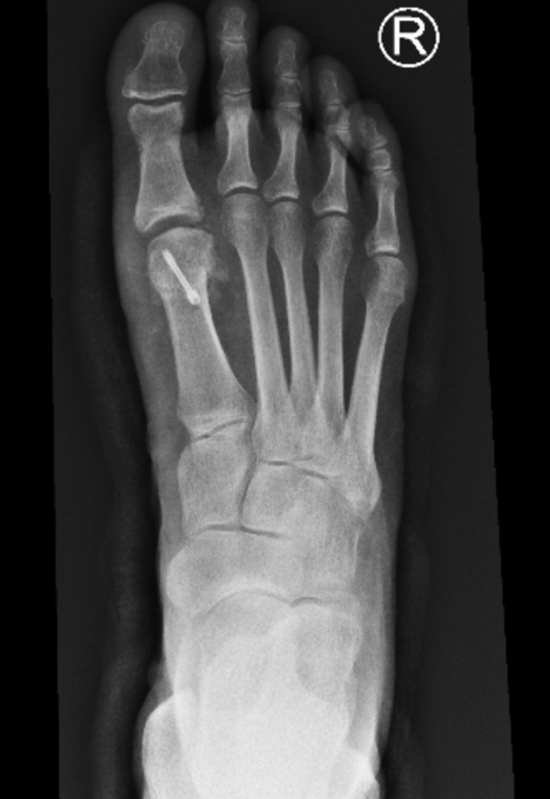

Figure 2: Post op x rays showing the joint remodelled (spurs removed) and the decompression osteotomy/bone cut allowing for improved joint motion